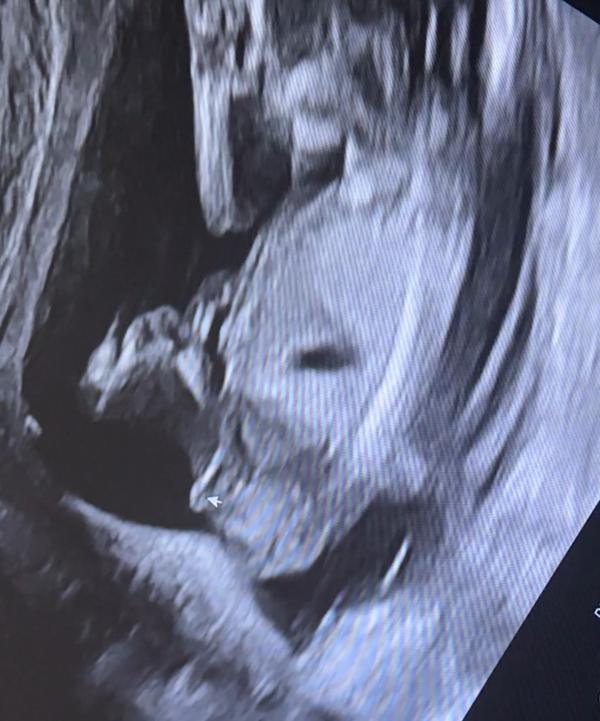

Помогите разобраться! Что такое половой бугорок и как его правильно интерпретировать? Советы экспертов

Эксперты, нужно ваше мнение))) кто понимает в половых бугорках. Кто тут?))

Девочка 100%

Ну походу девка

Девочка

Мне тоже кажется девочка

На девочку похоже

Я не эксперт, но кажется девочка